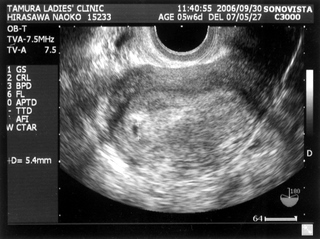

ちなみにこれは

、そらの一回目の検診時のエコーです。

4週の時です。ちいちゃい!